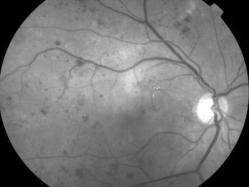

rétinopathie diabétique pré-proliférante

IM000001.jpg